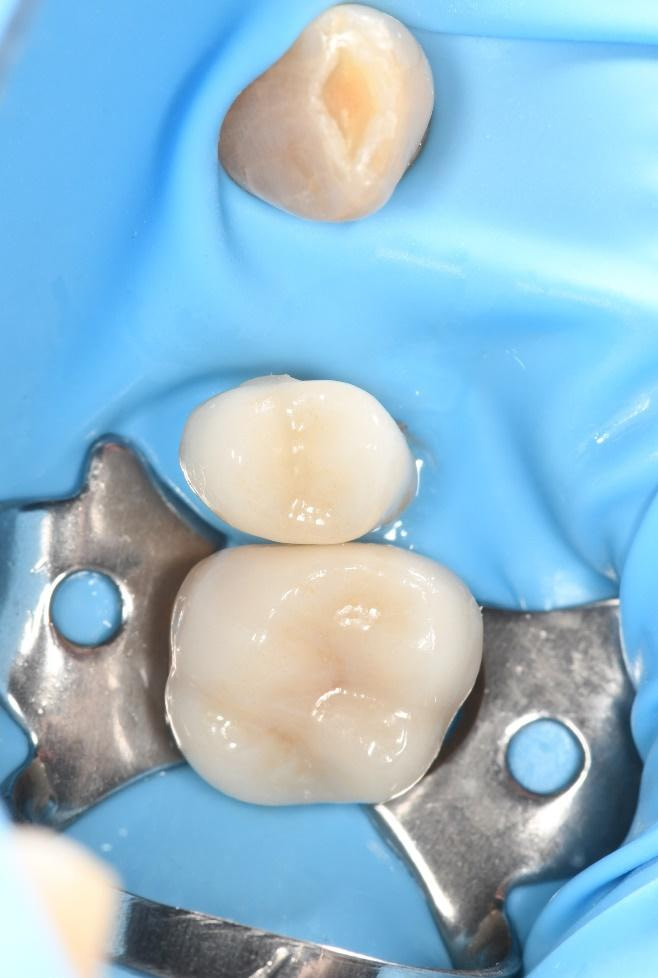

The crown was milled from a high-strength, multilayered zirconia and hand-finished to achieve a lifelike appearance.

At the final appointment, the crown was securely attached to the implant, resulting in a beautiful, natural-looking restoration.